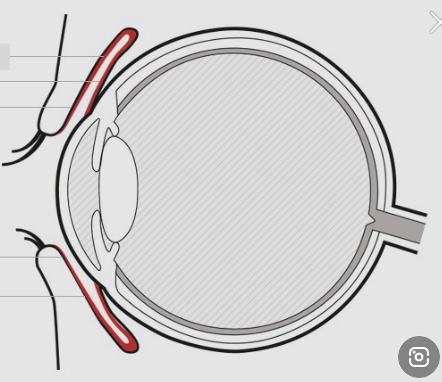

아래 그림에서 빨간색 부분을 보시면 결막이 안구 뒤쪽까지 연결되어 있지 않은걸 알 수 있습니다.